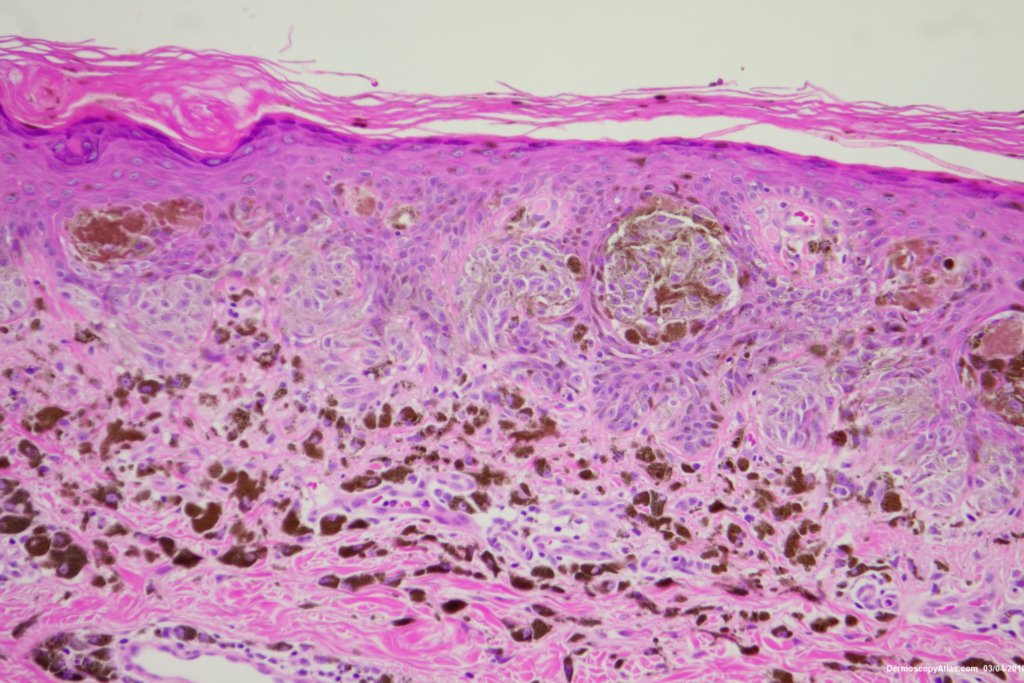

Diagnosis: Reed nevus

Sudden onset of a new pigmented lesion on the shoulder. Dermatoscopy shows an actively proliferating lesion with peripheral pseudopods that involve most of the circumference. Clinically this was either a Reed nevus or a Spitzoid melanoma. The histology favours a Reed nevus.